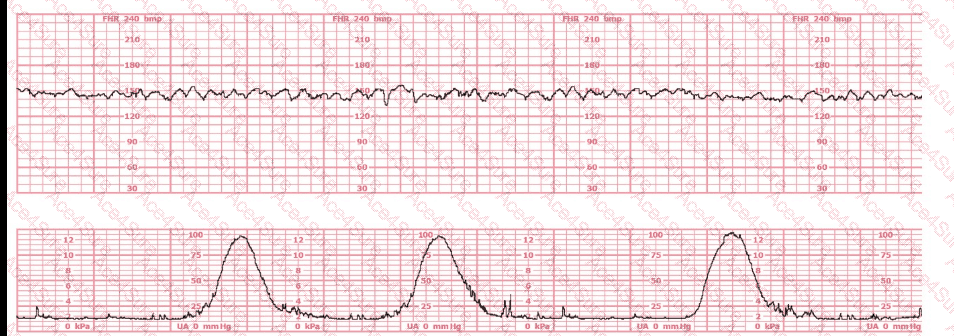

The fetal heart rate (FHR) tracing shown demonstrates a baseline approximately 135–145 bpm with fluctuations of 6–25 bpm, a hallmark of moderate variability. Moderate variability is defined in all NCC-endorsed resources as the normal amplitude range of 6–25 bpm around the fetal baseline.

The tracing provided does not show the repetitive, smooth, wave-like pattern of a sinusoidal rhythm; nor does it show flattening associated with minimal variability. Instead, it includes continuous beat-to-beat fluctuation within the moderate range, without periods of absent or minimal variability.

Therefore, based on NCC-standard definitions and the observed amplitude, the correct interpretation is moderate variability.